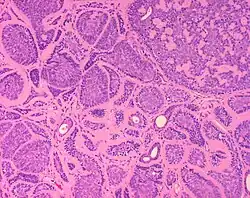

Micrograph of a dermal cylindroma in H&E stain. -

Dermal cylindromas are:

- Dermal lesions consisting of nests of cells that are surrounded by hyaline (i.e., glassy, eosinophilic, acellular) material and have:

- Hyperchromatic nuclei that may palisade (columnar nuclei arranged around the periphery of the cell nests with their short axis tangential to the nest periphery), and

- Cells with lighter staining ovoid nuclei at their centre.

They lack of a significant number of lymphocytes; this differentiates them from spiradenomas.